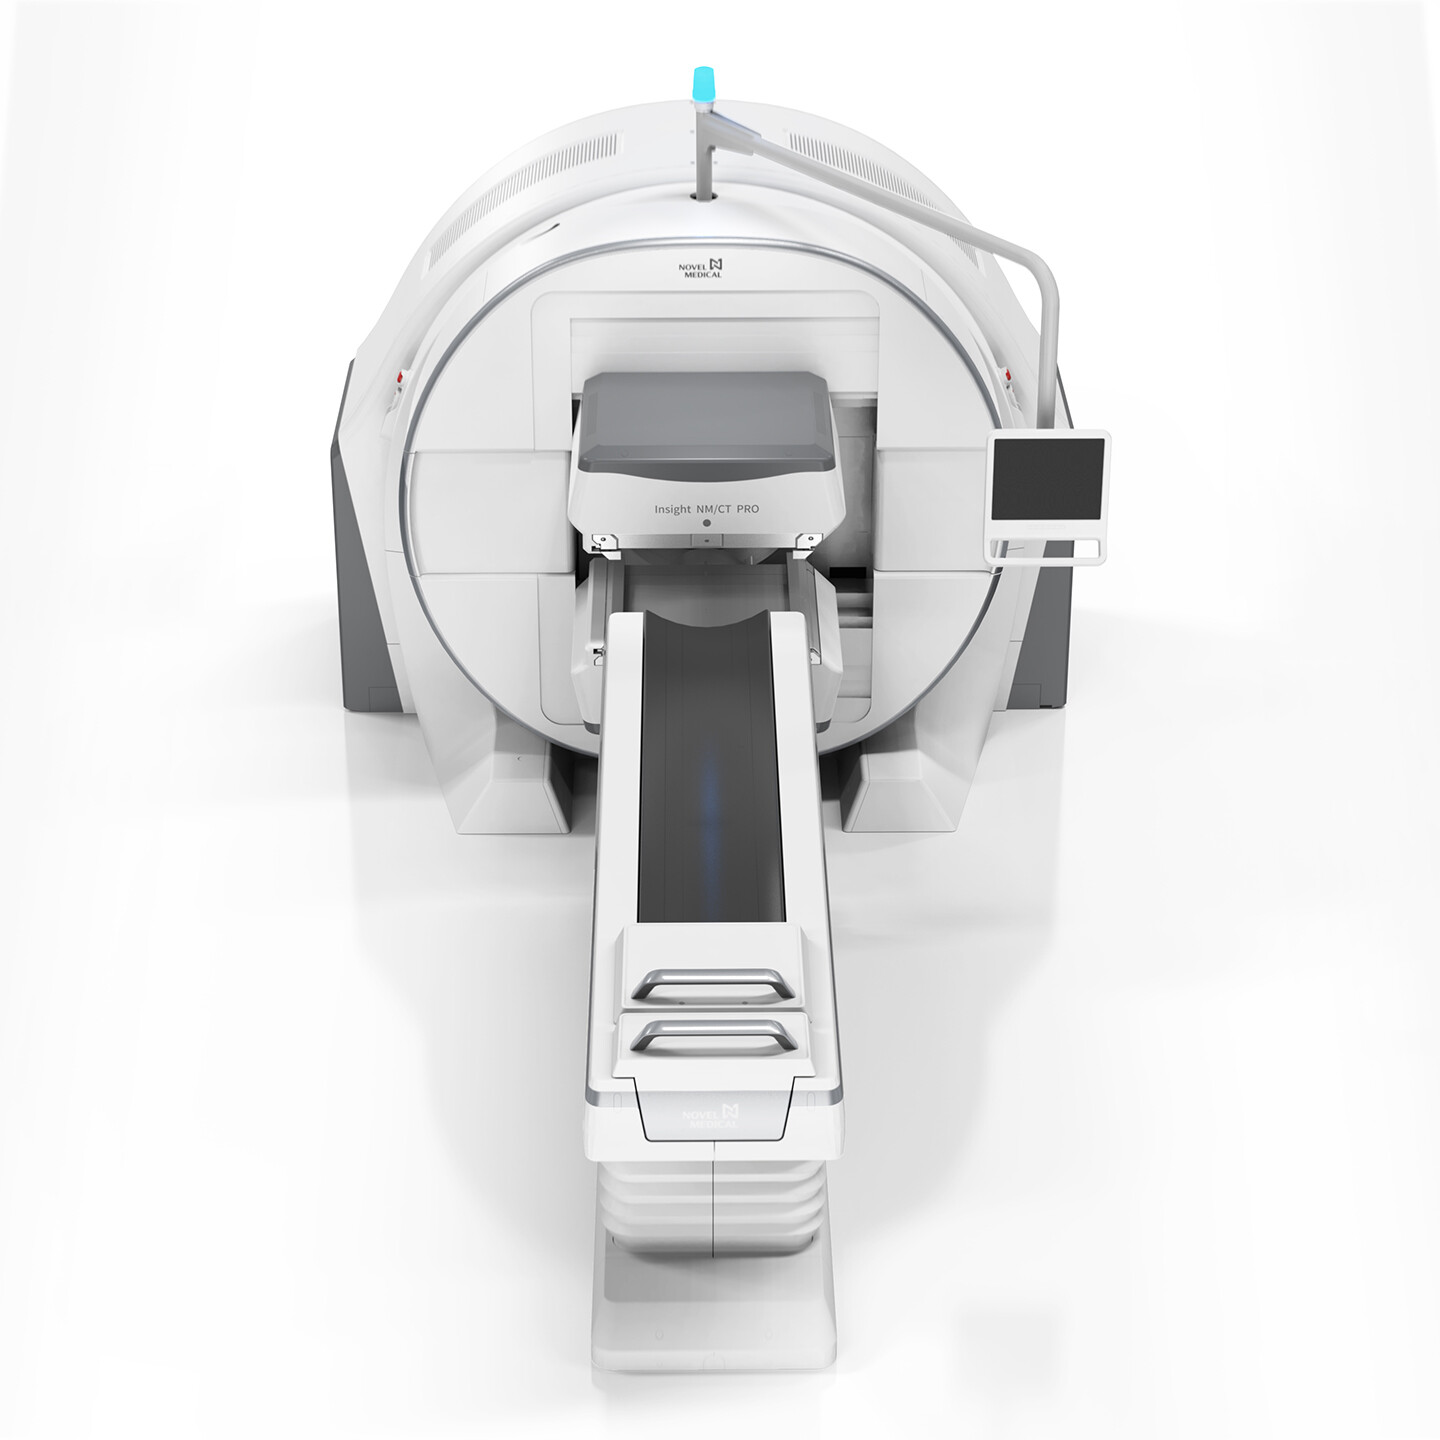

行业整体创新解决方案

摩登7咨询与设计以市场与技术的迭代更新为导向,业务深入智能制造、消费零售、交通出行、医疗健康、文化创意、公共服务等,多领域横向延伸,全行业覆盖。

摩登7是一家用咨询设计的能力,为垂直行业客户,提供产品创新价值的公司。摩登7坚持以用户体验为核心,致力于为企业提供行业整体创新解决方案。如需创新设计咨询,请联系专家团队。